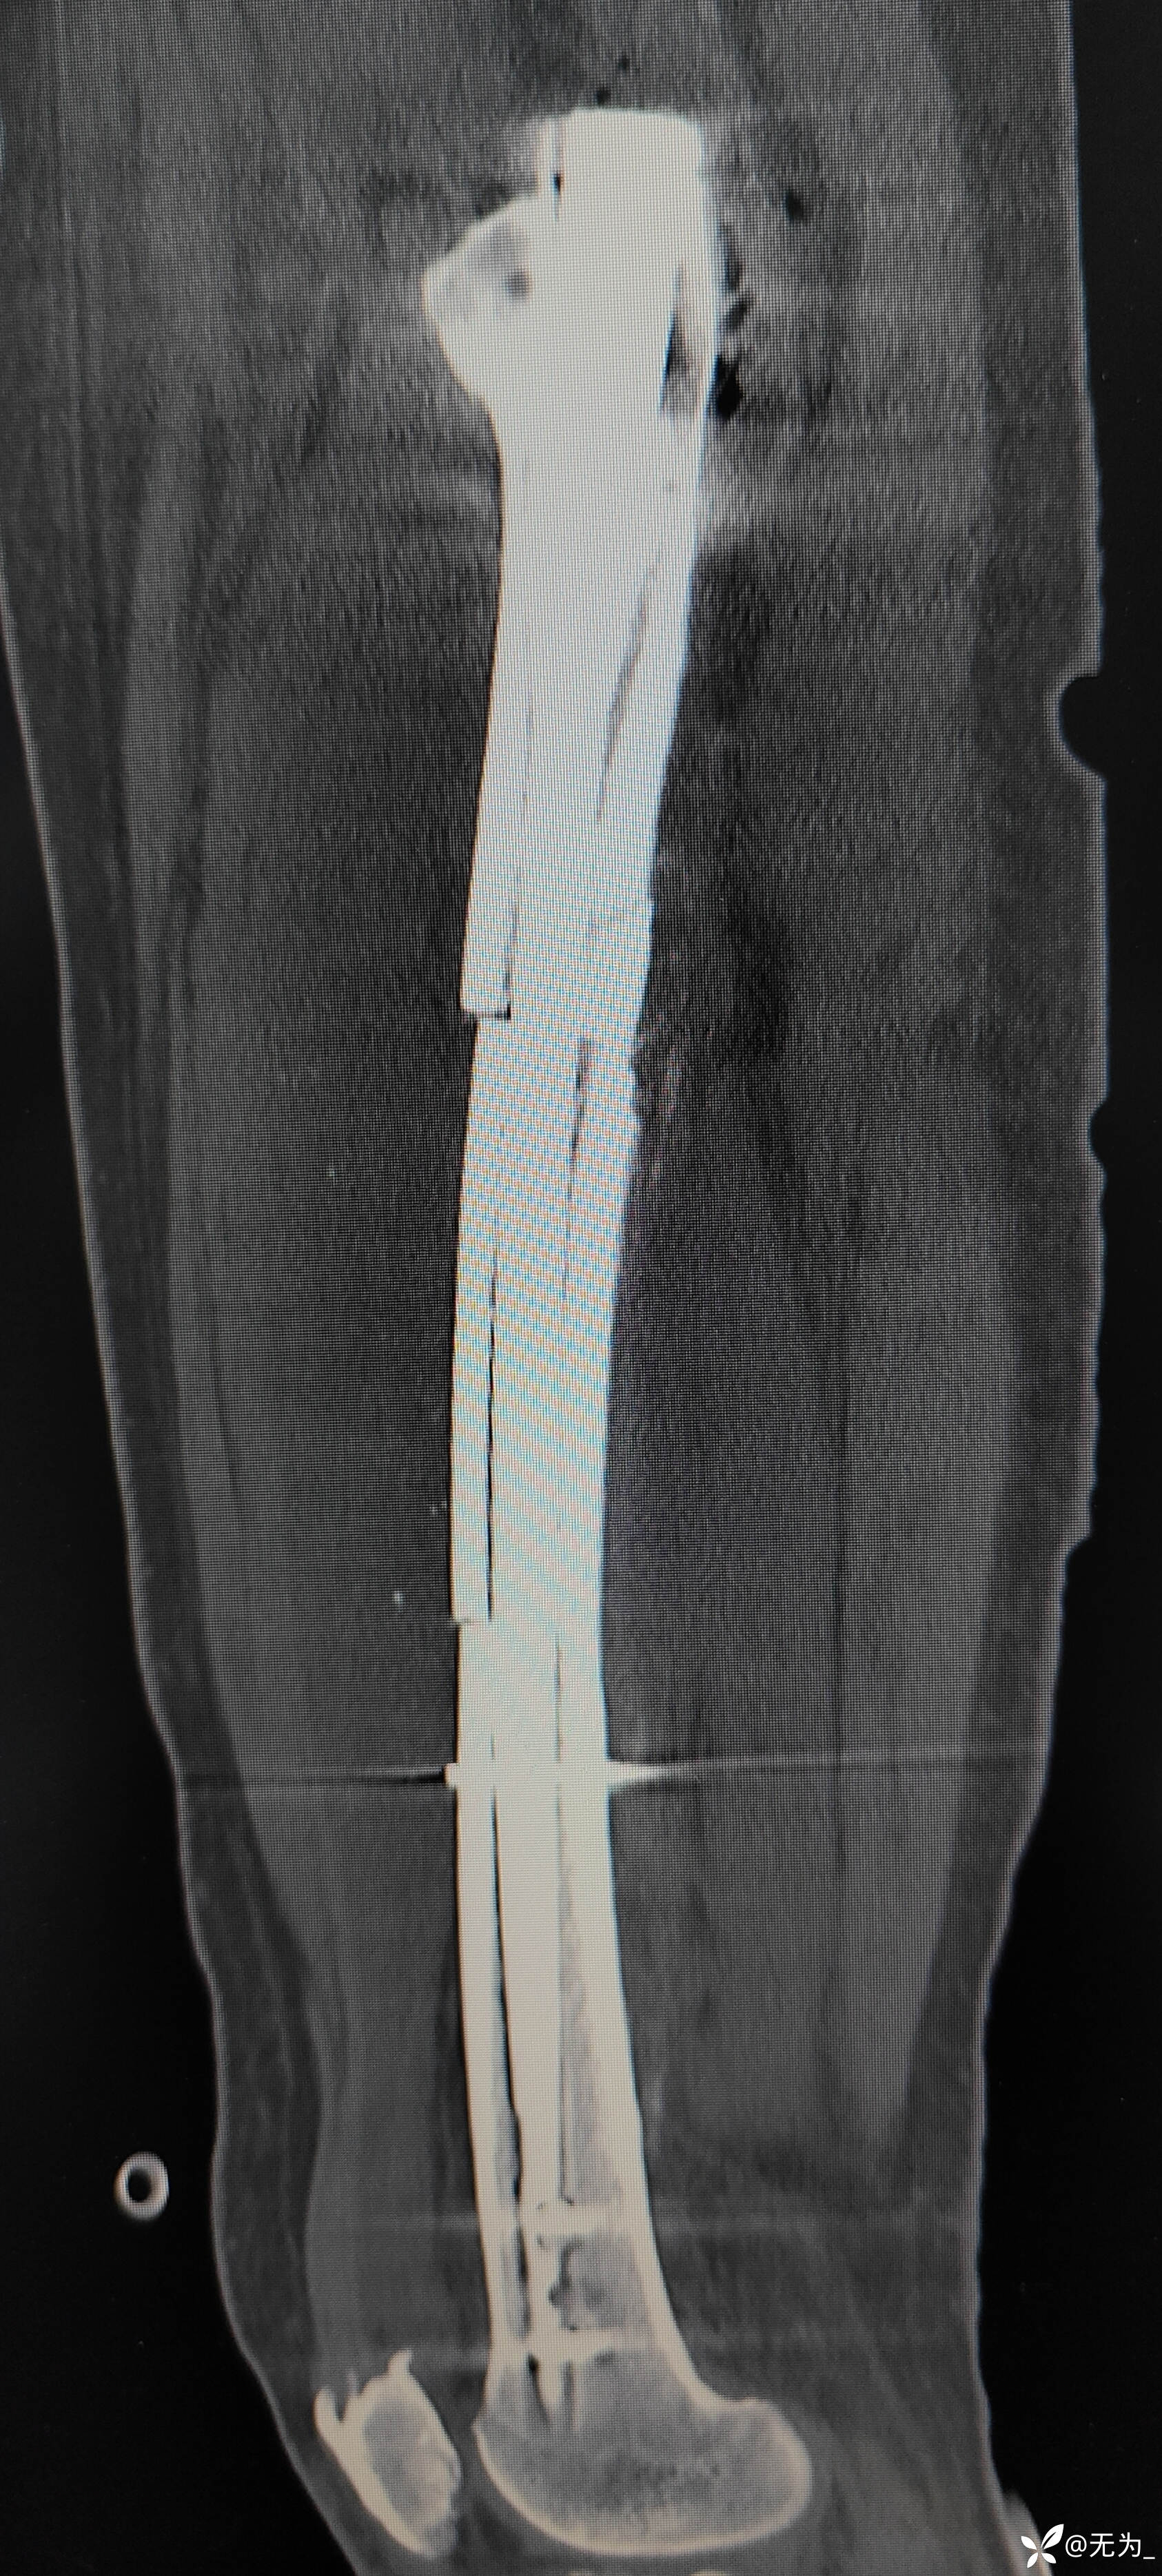

查体:右大腿中段前外侧两公分开放伤口,渗血,可处理游离骨块,大腿畸形、肿胀,足背动脉搏动可查。

三段骨折,复位困难且时间长,患者取侧卧位,取大腿外侧切口,切开以后大量肉芽组织,清理折断,牵引复位,远折断钛揽固定,近折端钳夹复位,开孔、扩髓,置入髓内钉,螺钉固定,内侧骨块未处理伴骨缺损,未植骨避免感染。